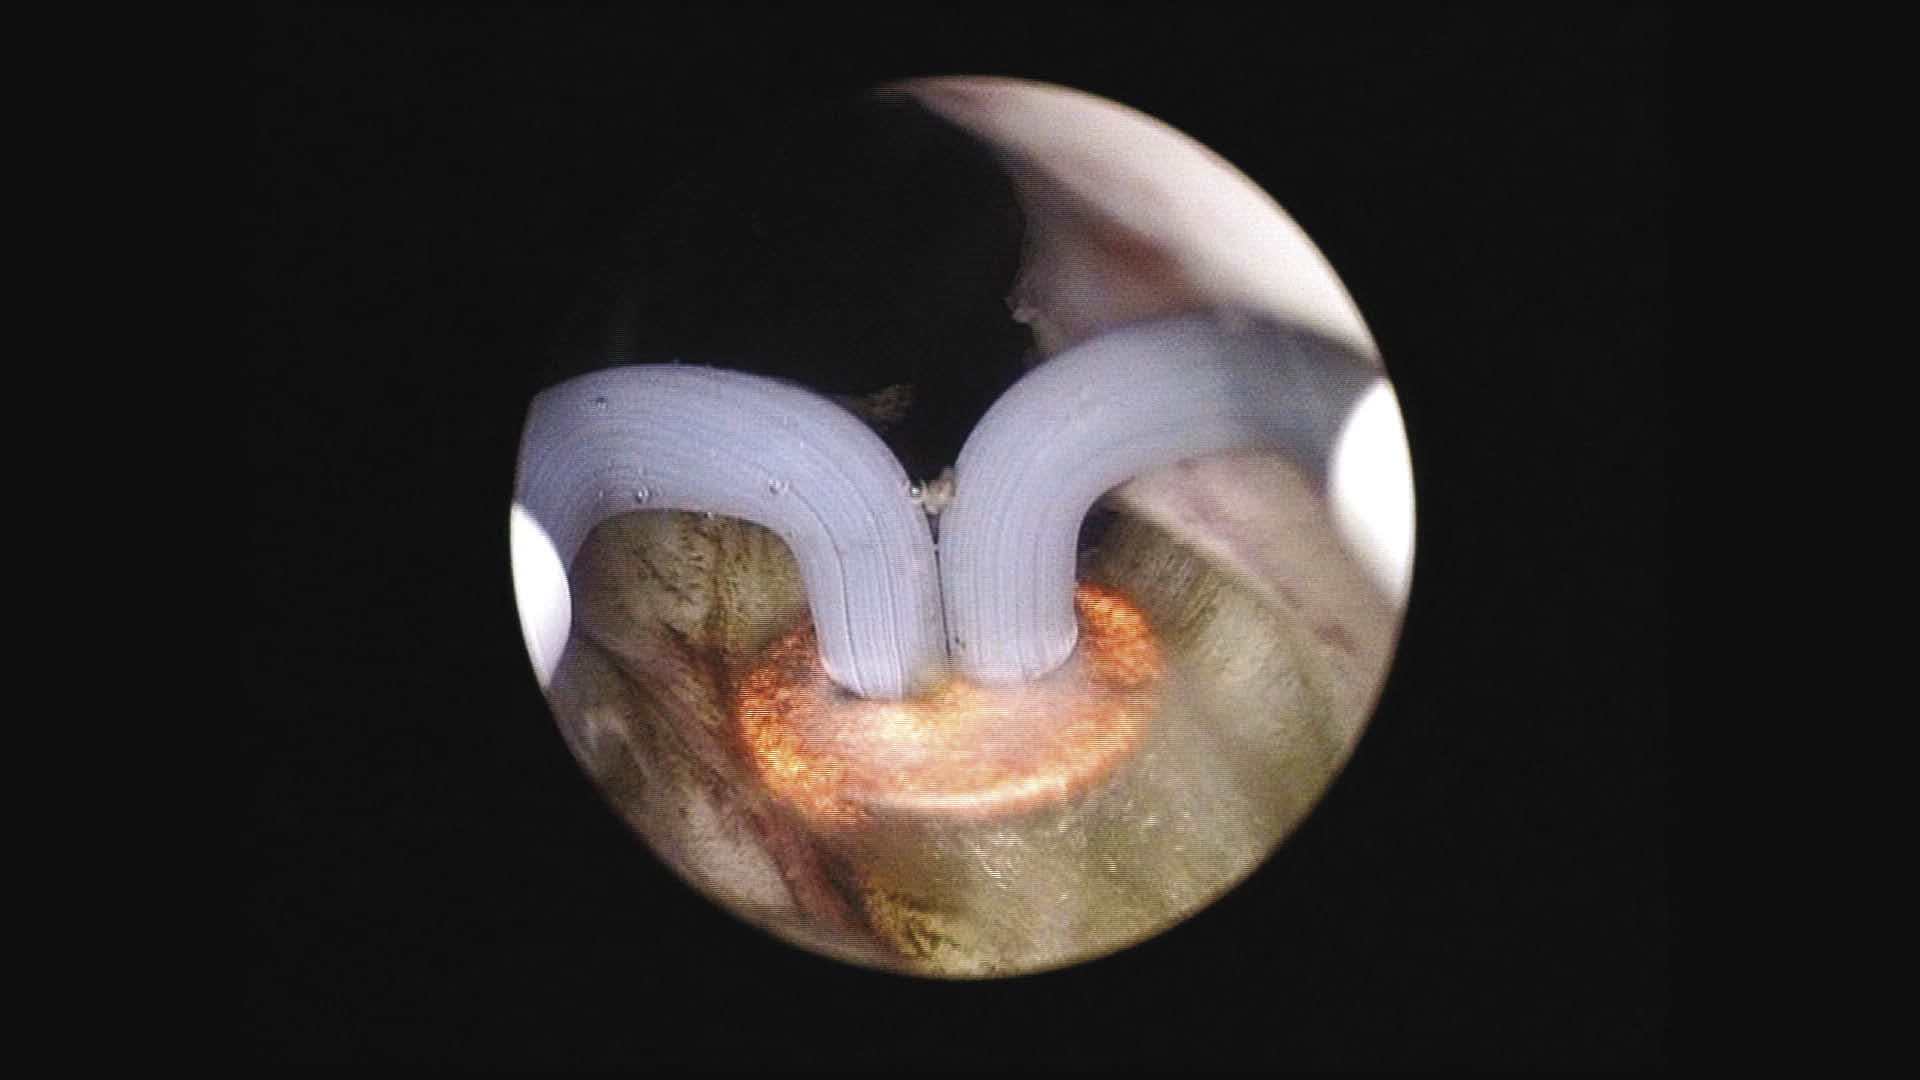

The procedure for vaporization is simple. The generator automatically sets the default settings for cut and coagulation, both of which are controlled using a foot pedal. Variations to the standard settings have not been needed. Operating room staff education is minimal and has been taken care of by the Olympus/ACMI representative prior to the first case. Long deep strokes with the PlasmaButton lead to large amounts of tissue being vaporized in a short period of time, Figure 2. Care must be taken to make sure that direct visualization of the PlasmaButton is maintained at all times to ensure no damage is done to the ureteral orifices, verumontanum, and/or external sphincter. Vaporization may be safely done in both the forward and backward motions of the PlasmaButton which further increases the efficiency of the procedure. Once adequate vaporization has been performed on the posterior aspect of the prostate, the lateral lobes are then vaporized again starting at the bladder neck and working back to the level of the verumontanum, but not beyond to ensure no damage is done to the external sphincter. If any anterior tissue needs to be vaporized it is then done after the lateral lobes have been dealt with.

Figure 2. Early vaporization on the median lobe. Image of the PlasmaButton corona.

HOW-DO-IT-Fig2.jpg